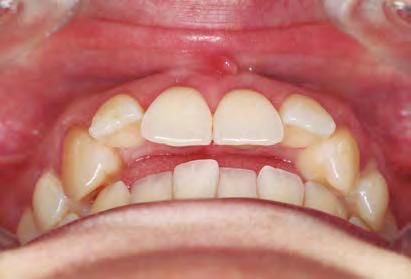

Ortodoncia interdisciplinar, un enfoque colaborativo para el tratamiento integral de maloclusiones

Es un hecho que la práctica de tratamientos de Ortodoncia interdisciplinar ha aumentado en los últimos años. Esto se debe a una combinación de avances en la tecnología y técnicas de tratamiento, a una mayor conciencia sobre la importancia de una salud oral integral, a una mayor demanda de tratamientos estéticos y a una mayor disponibilidad de tratamientos de Ortodoncia. Todo ello hace que la Ortodoncia interdisciplinar tenga hoy en día mayor relevancia que nunca y esto es algo que podremos comprobar en una de las citas científicas del año: el 69 Congreso que la Sociedad Española de Ortodoncia (SEDO) celebrará, entre el 7 y 10 de junio en Bilbao, y cuyo tema principal será «Ortodoncia interdisciplinar. La llave del éxito en el tratamiento del paciente adulto».

Los avances en la tecnología y las técnicas de tratamiento están permitiendo a los especialistas en Ortodoncia abordar problemas más complejos y tratarlos de manera más efectiva. Estos avances han facilitado la colaboración entre diferentes especialistas, lo que ha impulsado el desarrollo de la Ortodoncia interdisciplinar. Al mismo tiempo, llevamos años notando una

mayor demanda de tratamientos estéticos, de pacientes que están buscando tratamientos de ortodoncia que no solo mejoren su salud oral, sino también su apariencia. Todo ello junto a una mayor disponibilidad de tratamientos de ortodoncia, hace que sea muy común que los pacientes busquen tratamientos más especializados y personalizados que aborden todas sus necesidades específicas. Y, para dar respuesta a todo ello, el

trabajo del ortodoncista con otros especialistas es imprescindible.

Para el Dr. Eduardo Espinar Escalona, médico estomatólogo y ortodoncista, «en la actualidad, la tendencia es el manejo multidisciplinar. Son muchas las disciplinas, cada vez más complejas, que necesitan la intervención de diferentes profesionales. Creo que casi todos los pacientes adultos, y en ocasiones en crecimiento, necesitan una planificación multidisciplinar. Puesto que actualmente la mayoría de los tratamientos de nuestras consultas son pacientes adultos, eso es sinónimo de necesidades de abordaje interdisciplinar».